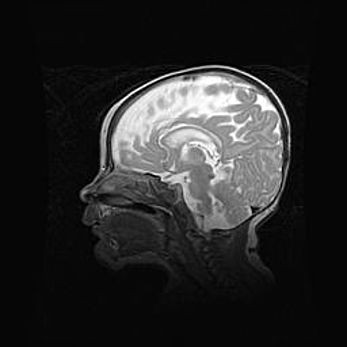

Наружная гидроцефалия с возможной атрофией височных областей.

Возраст: 28 дней

Вес: 3670 г

Пол: мужской

Окружность головы: 38 см

Срок гестации: 40 недель

Гидроцефалия головного мозга у новорожденных – это заболевание, которое характеризуется скоплением избыточного количества спинномозговой жидкости в желудочковой системе головного мозга в результате затруднения её перемещения от места выработки к месту поглощения в кровеносную систему или вследствие нарушения абсорбции. При открытой наружной форме гидроцефалии у новорожденных расширяются и переполняются субарахноидные пространства.

При нормотензивных  формах,  которые,  как  правило,  являются  следствием  перенесенных ишемических  повреждений  паренхимы  мозга,  возможно  сочетание микроцефалии  с нормотензивной гидроцефалией. В основе данных изменений лежит атрофия больших полушарий с преимущественной  локализацией  в  лобно-височных  областях.